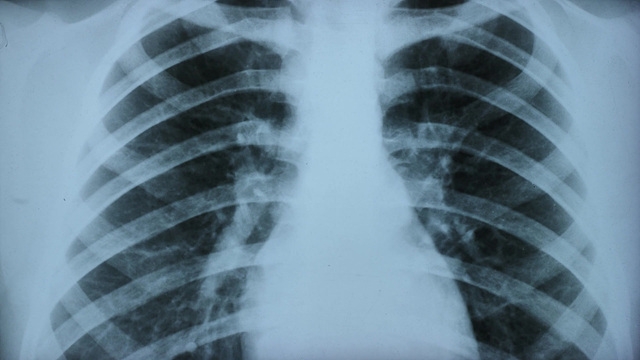

미국 도널드 트럼프 행정부가 추진하는 환경규제 완화 등의 정책이 미국인들의 폐질환을 증가시켜 조기사망을 확대시킬 수 있다는 연구결과가 나왔다.

미국 하버드의대, 케임브리지 건강협회, 메세추세스종합병원, 뉴욕시립대, UC샌프란시스코 등의 폐질환 전문의와 공중보건 전문가들이 참여한 이번 연구는 의료 접근성, 환경 규제, 백신 접종 등 10개 분야의 정책에 대해 분석해보니, 해당 정책들이 폐질환 발생률을 높이고 기존 질환을 악화시키며 치료 접근성을 약화시킬 수 있는 것으로 나왔다.

특히 트럼프 행정부가 1조달러(약 1500조원) 이상 규모의 보건 프로그램 예산을 삭감하며, 공공 건강보험 이용자 수백만명의 의료 접근이 차단될 수 있다는 분석이 나왔다. 예산 삭감이 저소득층의 백신 접종률 저하, 응급 치료 축소, 약물 접근성 감소로 이어질 수 있다는 설명이다. 아담 개프니 하버드의과대학 교수는 "미국인의 폐에 대한 공격"이라며 "향후 몇 년간 수백만명이 불필요하게 사망할 수 있다"고 했다.

대기오염 규제 완화도 주요 요인으로 지목됐다. 연구진은 그을음, 수은, 차량 배출가스 기준 완화가 천식 증가와 호흡기 질환 입원 확대를 초래할 수 있다고 밝혔다. 하버드대학교 기후·보건 및 글로벌환경센터 소장 메리 브라이스는 "오염 기업의 경제적 이익이 미국인의 호흡기 건강보다 우선되고 있다"고 우려했다.

또한 청정에너지 사업 지연과 화석연료 발전소 운영 연장도 대기오염 증가 요인으로 제시됐다. 연구진은 이러한 조치가 장기적으로 폐 건강에 "되돌릴 수 없는 영향"을 미칠 수 있다고 밝혔다.